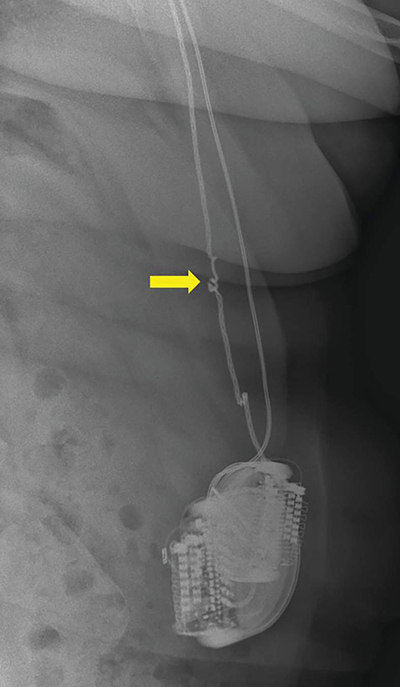

Teaching point: Twiddler's syndrome is a very rare but potentially disastrous complication after implantation of a neurostimulator or pacemaker, caused by twisting of the generator within the subcutaneous pocket, resulting in dislodgement and/or interruption of the electrodes that should be reported on x-ray.